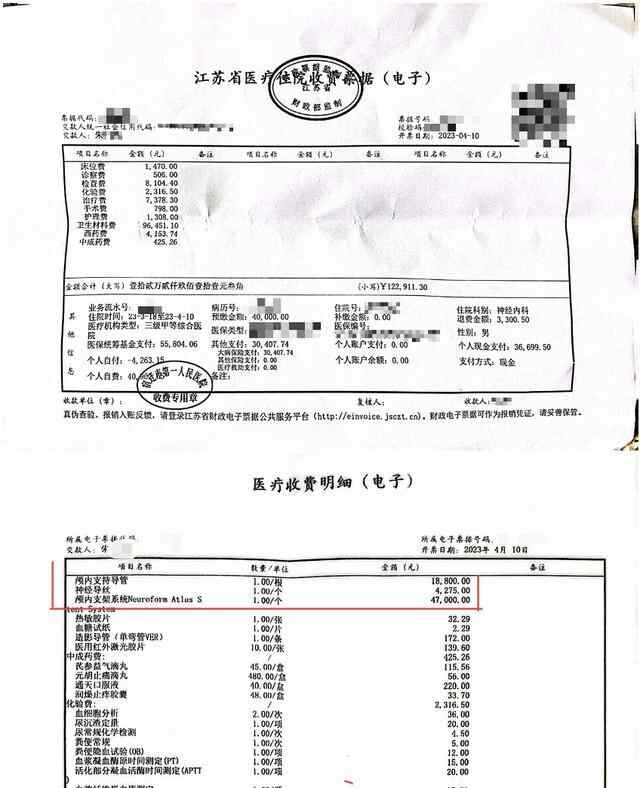

朱老汉接受经皮基底动脉支架植入术的手术记录及病程记录复印件。朱先生供图根据4月7日至4月10日的查房记录,朱老汉术后病情平稳,症状有所好转。4月10日,朱老汉出院,家属结清了住院医疗费用,合计12万余元,部分自费。

记者注意到,当日收费票据及相关明细中,卫生材料费近10万元,其中,Neuroform Atlas进口颅内支架47000元。

朱老汉的出院收费票据及部分明细。朱先生供图老人突然发病,医生承认支架植入失败5月4日,朱老汉突发严重脑梗。他先被救护车送至江苏省宿迁市泗洪县分金亭医院抢救。